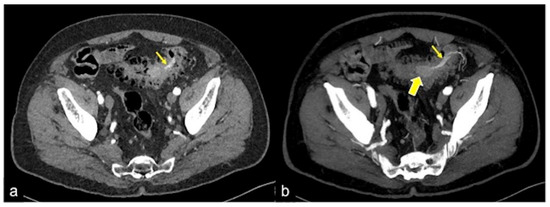

| Meckel’s Diverticulum (Figure 30) | Asymptomatic or, rarely, massive gastrointestinal bleeding. | A diverticulum with fluid or air content originating from the antimesenteric side of the distal ileum. |